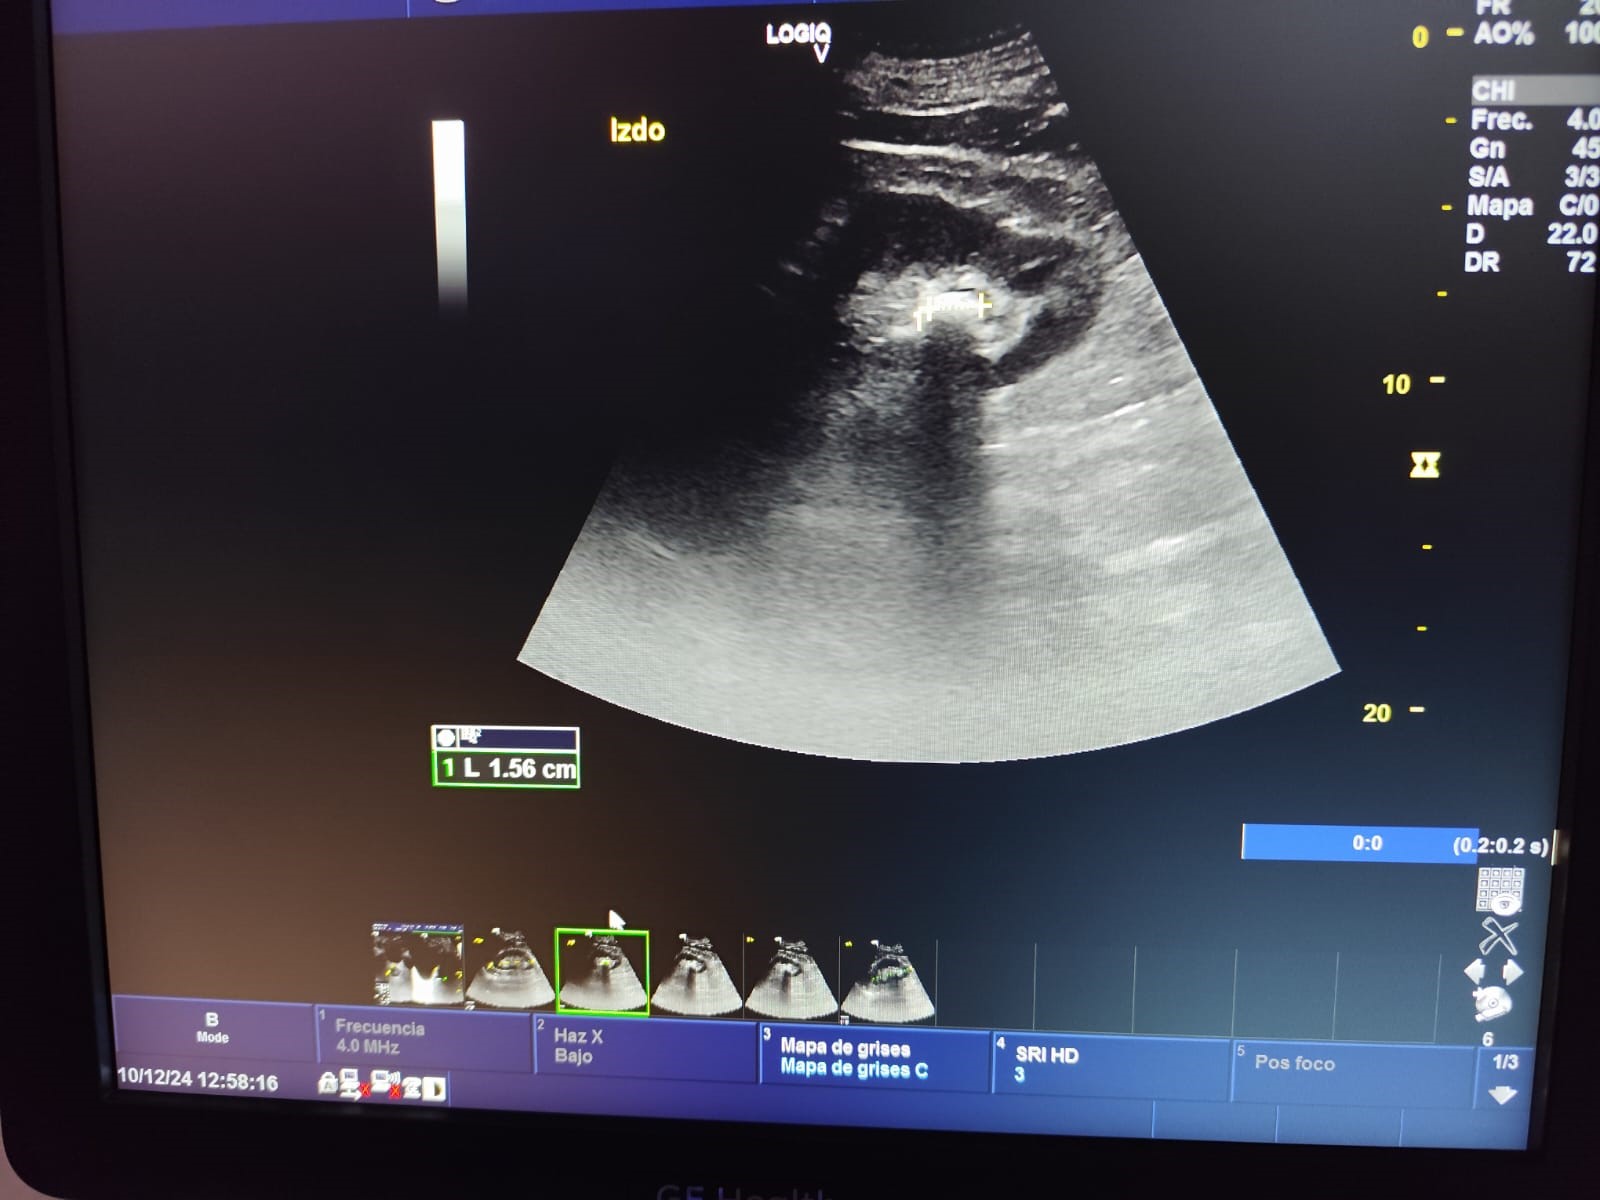

Ecografía en atención primaria (POCUS): Ecografía del riñón izquierdo: Litiasis de 1.4 cm en polo inferior, morfología y tamaño normales. Resto sin alteraciones.

Juicio clínico: Litiasis renal en riñón izquierdo, sin signos de hidronefrosis u otra complicación.

Realiza una nueva consulta por hematuria, sin aportar resultados de la prueba de imagen ya que se encuentra pendiente, por lo que se efectúa ecografía clínica en el Centro de Salud. El paciente realiza una videograbación del procedimiento ecográfico con el propósito de compartirla en la consulta de Urología, donde tras observar los resultados se remite a Litotricia Extracorpórea por Ondas de Choque.

En este caso podemos observar en un paciente de 62 años con hematuria asintomática, la importancia y la efectividad de haber realizado la ecografía en el centro de salud para el diagnóstico de litiasis y la ausencia de otras complicaciones. De esta manera ha demostrado que puede integrarse eficazmente en la consulta de atención primaria, permitiendo un diagnóstico rápido y preciso, reduciendo tiempos de espera y mejorando el manejo clínico. Es importante destacar que para ello se requiere una formación del personal médico adecuada y equipos de calidad.